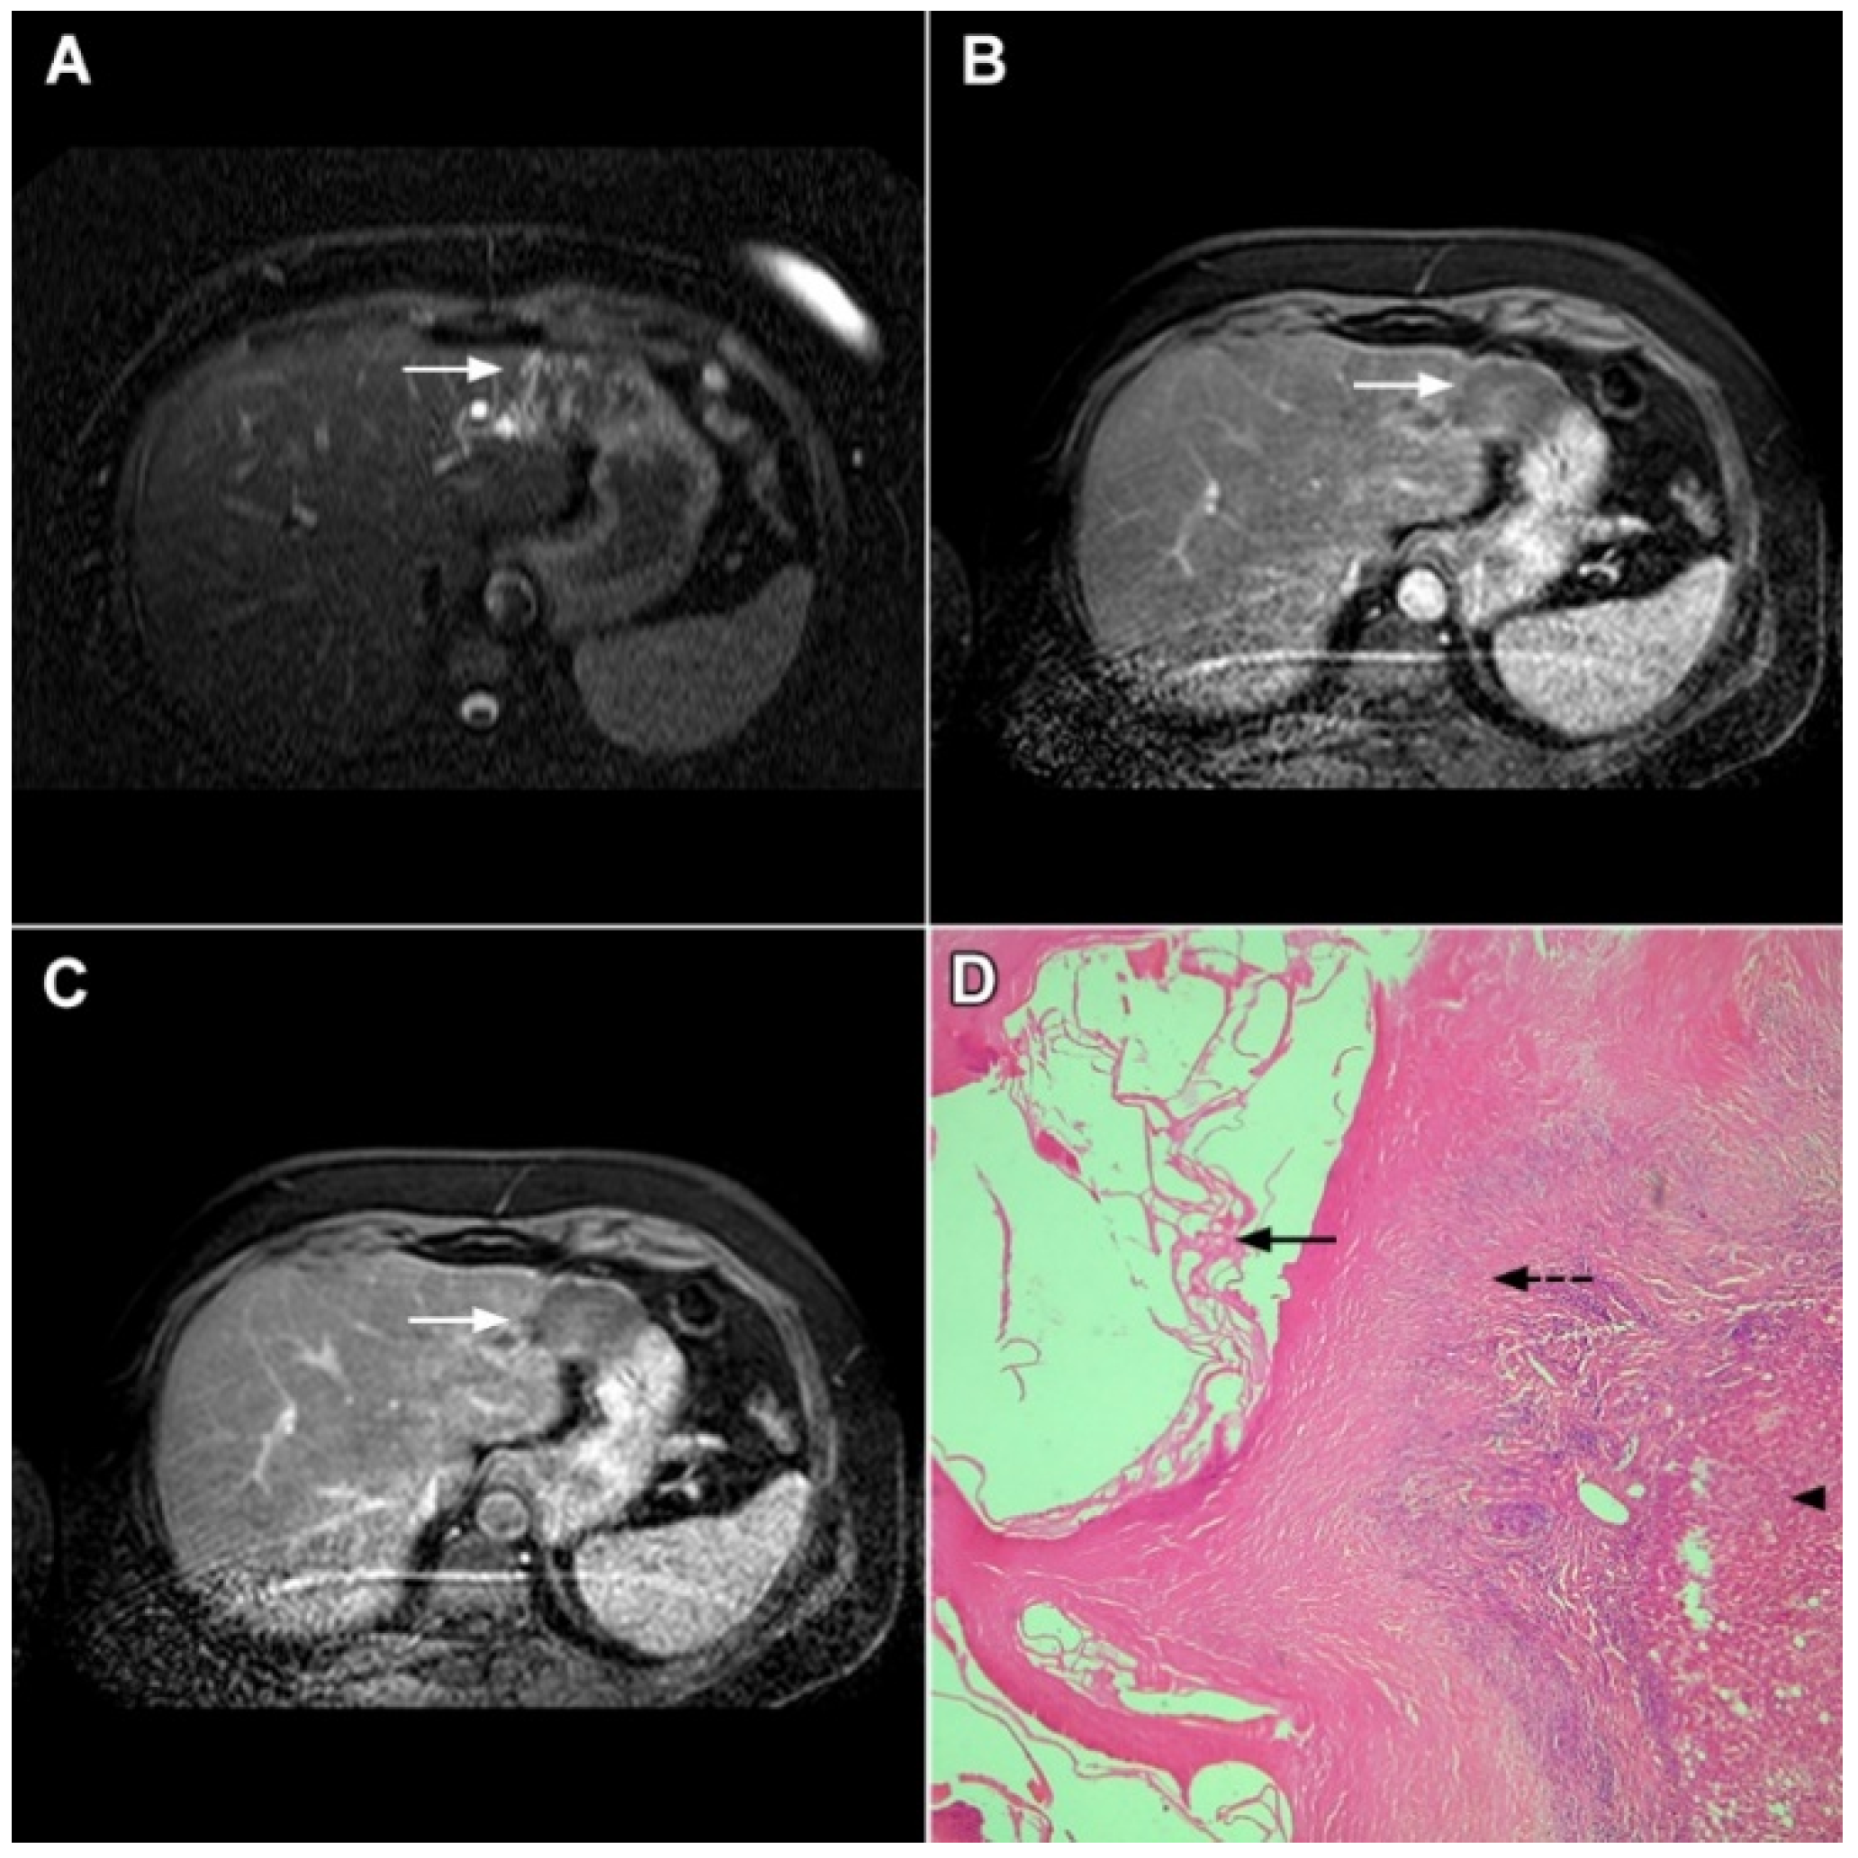

3.1.5. Liver Echinococcosis

3.2. Malignant Lesions

3.2.1. Solitary Hypovascular Liver Metastasis

3.2.4. Hemangioendothelioma

3.2.5. Primary Hepatic Lymphoma